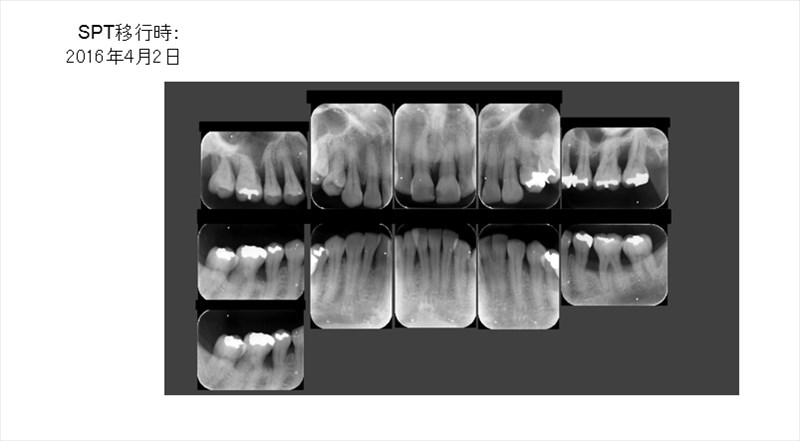

歯周病のプログラムを当院で受けて頂き特に再生療法の様な手術もせずこのように骨が再生しています。

勿論劇的に歯周ポケットは改善しています。

メンテナンスに移行する際のレントゲン

骨が平坦になり歯ブラシのしやすい形態になって今年も安定しています。術後4年、問題なく1本も歯を失っていません。